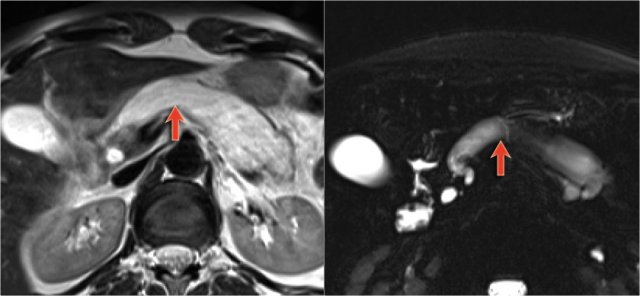

Normal T2WI and heavily T2WI with fatsat of a large main duct IPMN with extremely dilated pancreatic duct.

There is obstruction of the common bile duct with dilatation of the intrahepatic bile ducts (blue arrows).

Notice the extremely widened main pancreatic duct (red arrow).

This patient presented with pancreatitis.